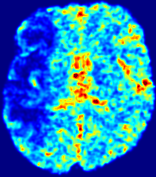

4.3.2 Diffusion Imaging via Advection-Diffusion

Slice #1Slice #2Slice #3Slice #4Slice #5Slice #6Dgtsuperscript𝐷gtD^{\text{gt}}Refer to captionRefer to captionRefer to captionRefer to captionRefer to captionRefer to captionDestsuperscript𝐷estD^{\text{est}}Refer to captionRefer to captionRefer to captionRefer to captionRefer to captionRefer to captionRefer to caption0.300.300.300.240.240.240.180.180.180.120.120.120.060.060.060.000.000.00(mm2/s)𝑚superscript𝑚2𝑠(mm^{2}/s)𝐕est𝟐subscriptnormsuperscript𝐕est2\|\bf{V}^{\text{est}}\|_{2}Refer to captionRefer to captionRefer to captionRefer to captionRefer to captionRefer to captionRefer to caption0.00300.00300.00300.00240.00240.00240.00180.00180.00180.00120.00120.00120.00060.00060.00060.00000.00000.0000(mm/s)𝑚𝑚𝑠(mm/s)

Figure 15: PIANO identifiability testing: diffusion imaging via advection-diffusion. Top row shows Dgtsuperscript𝐷gtD^{\text{gt}} used for simulating ground truth pure diffusion. Rows below show the estimated Destsuperscript𝐷estD^{\text{est}} and 𝐕est2subscriptnormsuperscript𝐕est2\|{\bf{V}}^{\text{est}}\|_{2} on corresponding slices. Note that the plotted value scale for 𝐕est2subscriptnormsuperscript𝐕est2\|{\bf{V}}^{\text{est}}\|_{2} is 0.01 of that for Dgtsuperscript𝐷gtD^{\text{gt}} and Destsuperscript𝐷estD^{\text{est}}.

Similarly, we test the behavior of PIANO when estimating both advection and diffusion from a pure diffusion-driven process. The goal is to determine if PIANO is able to recognize that there is only diffusion governing the given concentration time-series. We use the same ‘Diffusion Imaging’ data simulation of Sec. 4.2.1 as the concentration dataset, PIANO estimates both velocity 𝐕estsuperscript𝐕est{\bf{V}}^{\text{est}} and diffusivity Destsuperscript𝐷estD^{\text{est}}. Estimation results in Fig. 15 confirm PIANO’s identifiability again: the estimated 𝐕est2subscriptnormsuperscript𝐕est2\|{\bf{V}}^{\text{est}}\|_{2} is almost invisible compared to Destsuperscript𝐷estD^{\text{est}}, even plotted with a 1%percent11\% value range compared to that for Destsuperscript𝐷estD^{\text{est}}. On the other hand, Destsuperscript𝐷estD^{\text{est}} achieves comparable estimation performance as ‘Diffusion Imaging via Diffusion’ in which PIANO predicts Destsuperscript𝐷estD^{\text{est}} alone (shown in Fig. 13).